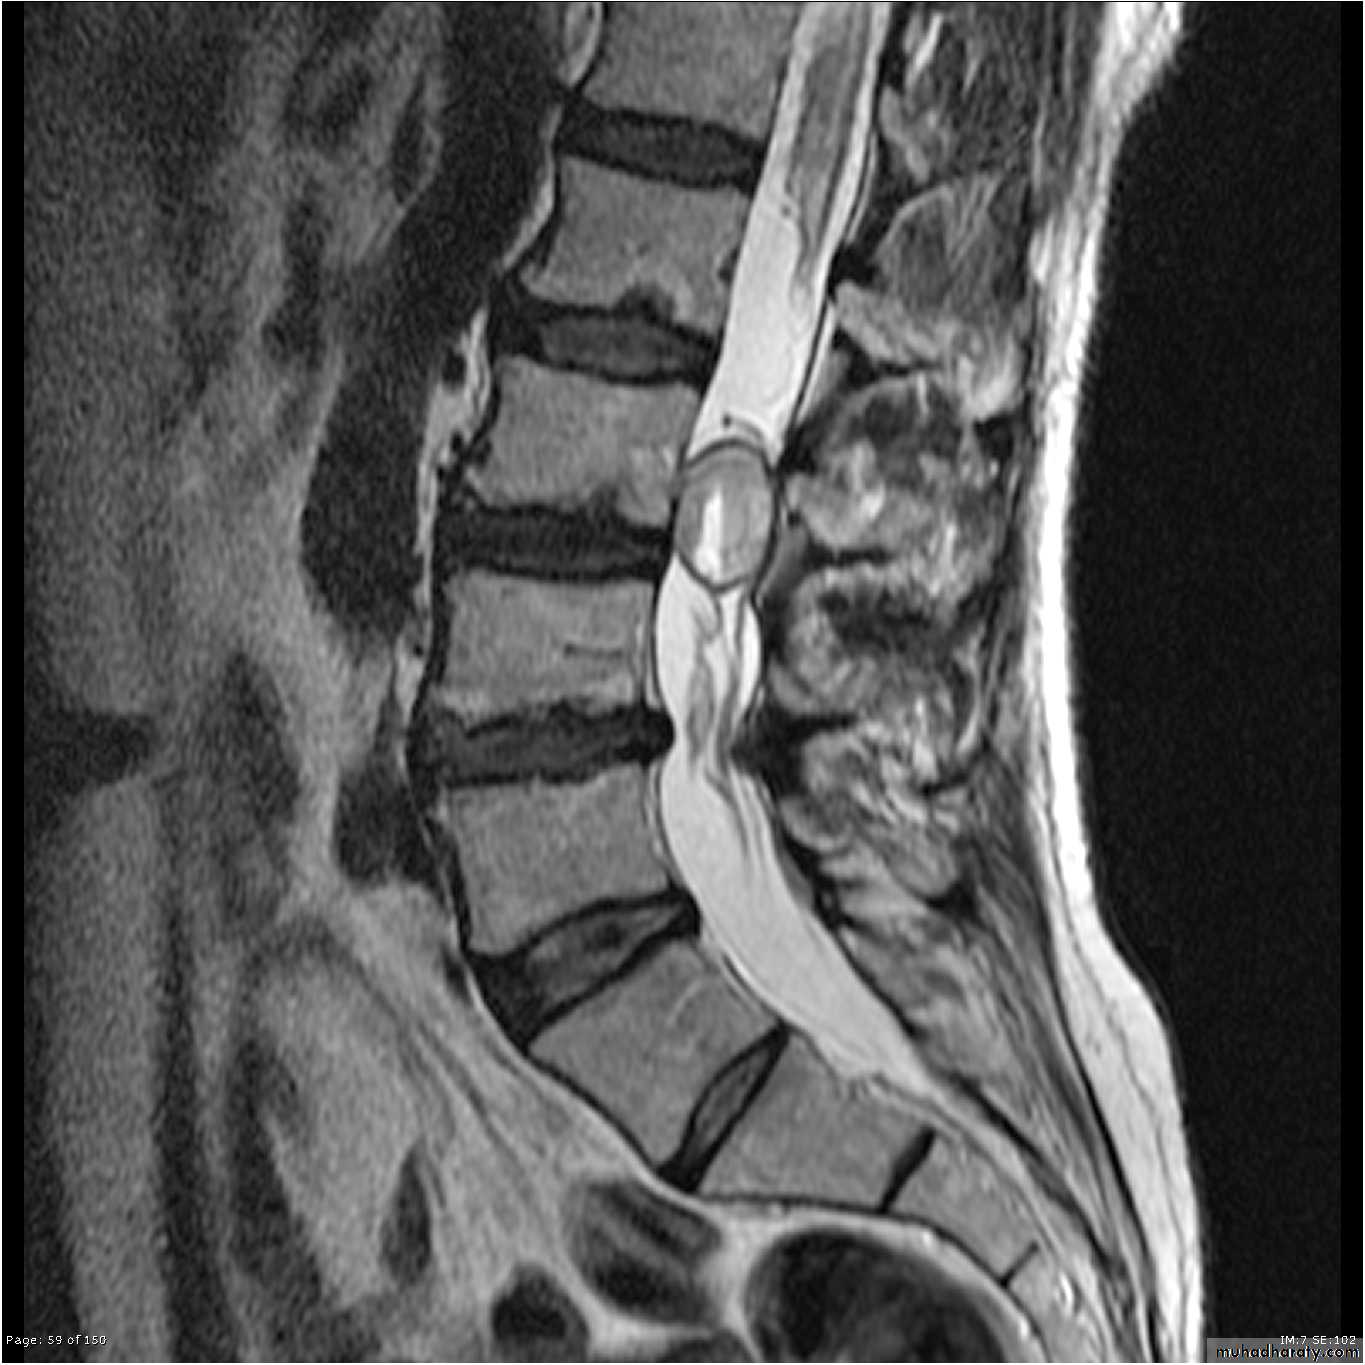

X-rays: show an abnormal narrowed disc space and to exclude bone diseases. After several attacks the disc space may be narrowed and small osteophytes appear.CT and MRI are more reliable than myelography.

CHRONIC INTERVERTEBRAL DISC DEGENERATIONMRI:

Bulging of the annulus fibrosus in both sagittal and axial projections and diminished thickness and reduced signal intensity (dehydration) of the degenerating disc.

Imaging:X-rays will show features of disc degeneration or spondylolisthesis. Measurement of the spinal canal can be carried out on CT and MRI.